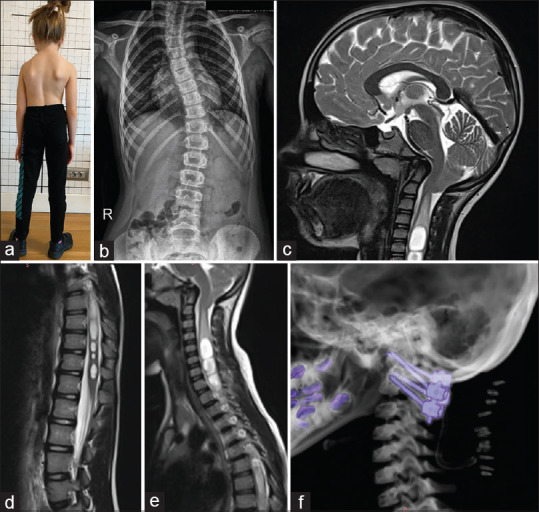

特发性脊柱侧凸(IS)通常与Chiari畸形(CM)和脊髓空洞相关,这些疾病被认为有一个共同的潜在原因:寰枢椎不稳定。寰枢稳定最近成为一种新的治疗选择。一名4岁女孩,表现为进行性脊柱侧凸(Cobb角28.6°)、颈部疼痛、CM和脊髓空洞。患者被诊断为寰枢中心或轴向不稳定,并接受C1-C2固定。术后,患者颈部疼痛明显缓解。随访显示进行性鼻窦缩小,x光显示Cobb角在18个月内下降至21°。本病例强调了寰枢椎稳定在IS合并CM和脊髓空洞的患者中阻止脊柱侧凸进展的潜力。与传统的多节段稳定不同,C1-C2固定提供了一种微创方法,并保留了生长年龄患者的脊柱活动能力。IS合并CM和脊髓空洞的病例应考虑寰枢椎不稳定。寰枢椎单独稳定可提供有效的治疗,并具有良好的临床和放射学结果。

Idiopathic scoliosis (IS) is frequently associated with Chiari malformation (CM) and syringomyelia, conditions thought to share a common underlying cause: Atlantoaxial instability. Atlantoaxial stabilization has recently emerged as a novel treatment option. A 4-year-old girl presented with progressive scoliosis (Cobb angle of 28.6°), neck pain, CM, and syringomyelia. The patient was diagnosed with central or axial atlantoaxial instability and underwent C1-C2 fixation. Postoperatively, she experienced significant relief from neck pain. Follow-ups demonstrated progressive syrinx reduction, while X-rays revealed a Cobb angle decrease to 21° in 18 months. This case highlights the potential of atlantoaxial stabilization to halt scoliosis progression in IS patients with CM and syringomyelia. Unlike traditional multisegmental stabilization, C1-C2 fixation offers a minimally invasive approach and preserves spinal mobility in growth-age patients. Atlantoaxial instability should be considered in IS cases with CM and syringomyelia. Atlantoaxial stabilization alone may provide effective treatment with favorable clinical and radiological outcomes.